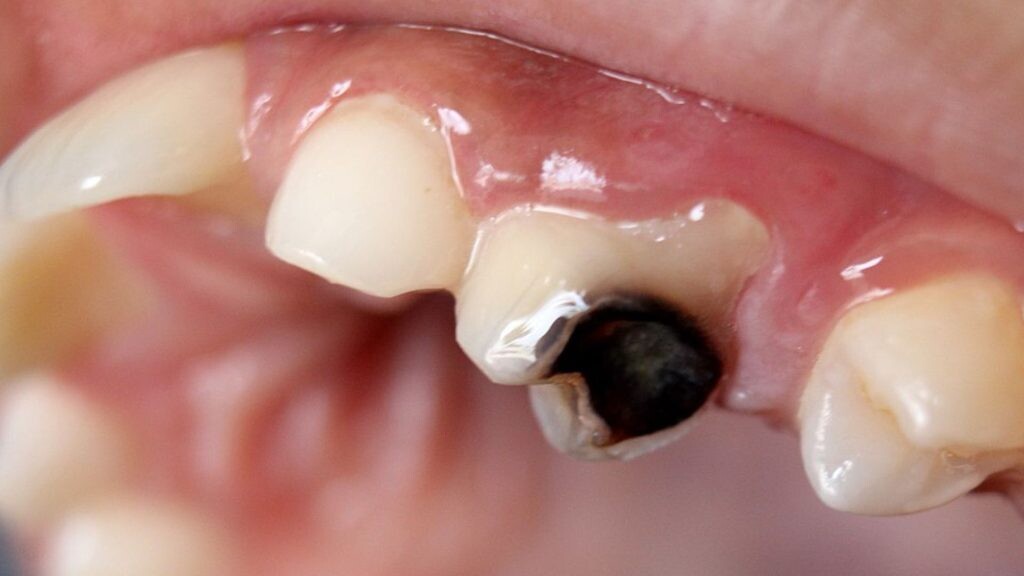

Enamel Damage can result in black teeth

Decay or cavities are the most common reason for teeth turning black. When the pulp becomes infected, the black color begins inside the tooth and works its way to the surface. The black appearance often starts as a few dark spots, but when left untreated, the whole tooth can turn black. Turning black is usually a gradual transformation that begins with brown or gray spots or small dots of black near the gum line.

An injury to the mouth can damage the tooth so badly that it dies, in which case the tooth may also turn black.

Tartar and Stains

Tartar that develops on the outside of the molars or inside the front teeth can build up stains and erode holes in the teeth and make them look black.

Dental Treatment

Brushing twice a day and flossing is a good preventative. A dentist can clean your teeth and scrape away the tartar buildup. Other options are filling cavities or in some instances, getting a root canal and crowning a tooth. When the tooth can’t be saved, extraction may be necessary.